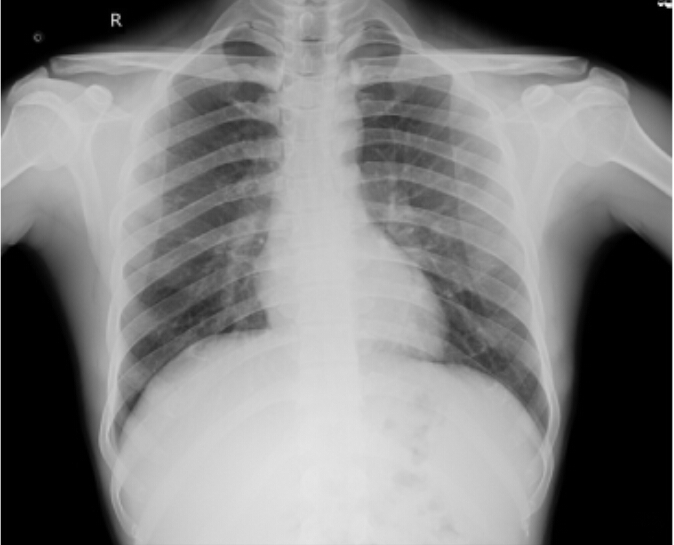

RS : Bilateral air entry present,normal vesicular breath sounds heard